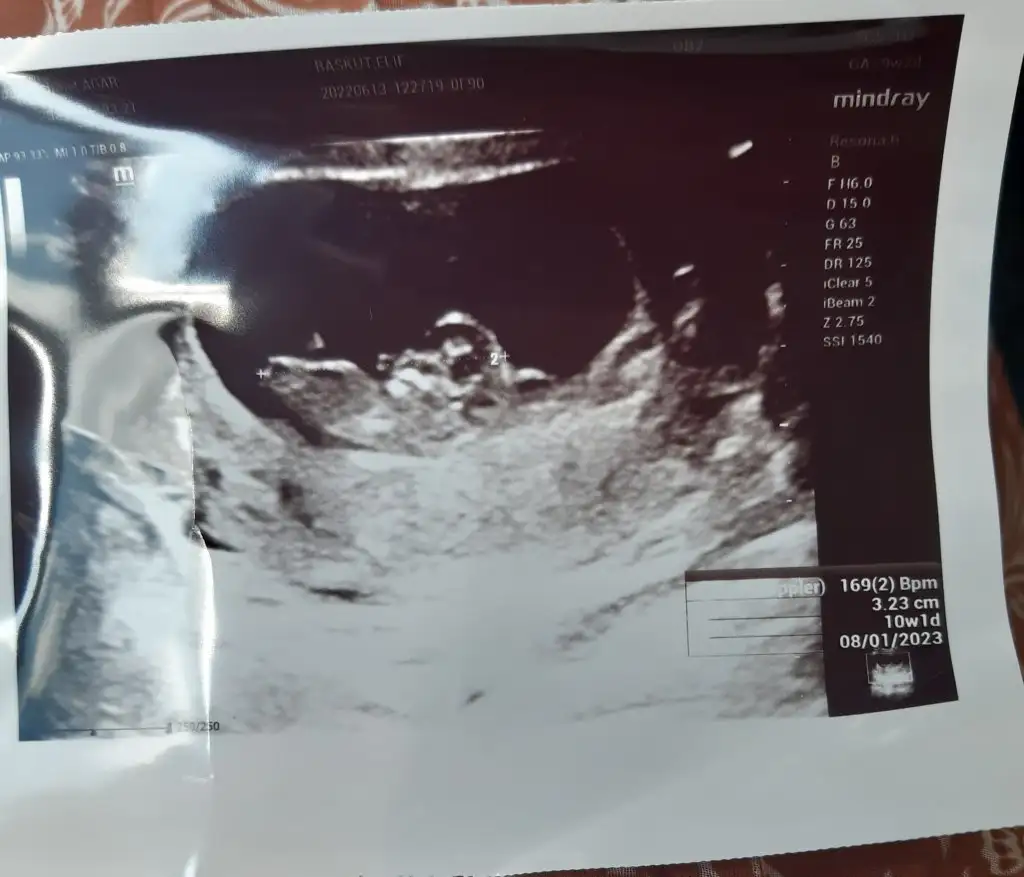

Kızlar çıktım az önce doktordan icerdeki kanama alanım hala var dedi ama büyümemiş aynı duruyor sadce ilaçlara ve yatmaya devam 10+1 çıktı ultrasondan başı kolları falan oluşmuştu çok tuhaf oldum 😃😃 şimdilik yolunda hersey 🥰🥰